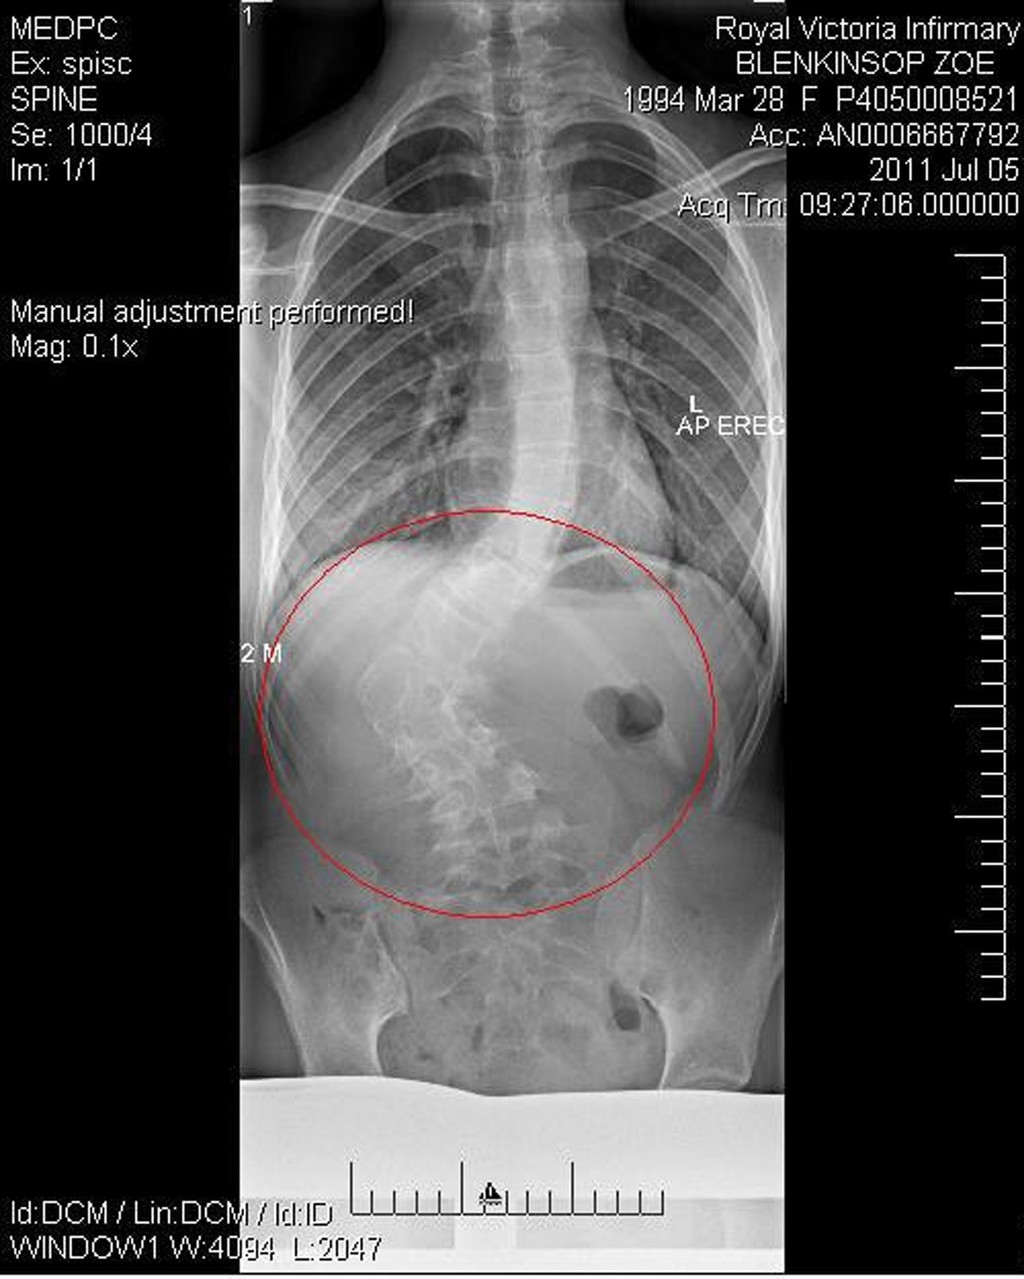

Pri pohľade na fotografie pekného a sebavedomého dievčaťa by ste si asi nemysleli, že si prešla v živote peklom. Trápila ju ťažká skolióza. Chrbticu mala takú krivú, až sa jej vytvoril hrb. Zároveň mala aj problém s chôdzou. Čo však Zoe Blenkinsop trápilo viac, bol posmech celej školy.

Zoe, pochádzajúca z anglického mesta North Shields, prosila lekárov o operáciu už od jedenástich rokov. Museli však počkať, kým prestane rásť. Nakoniec ju absolvovala v 18-tich rokoch.

Zákrok trval sedem hodín a krušné detstvo jej pripomína jazva, ktorá sa tiahne pozdĺž chrbtice. Dnes chodí normálne, vďaka rovnej chrbtici je vyššia a zatúžila po nej aj modelingová agentúra.